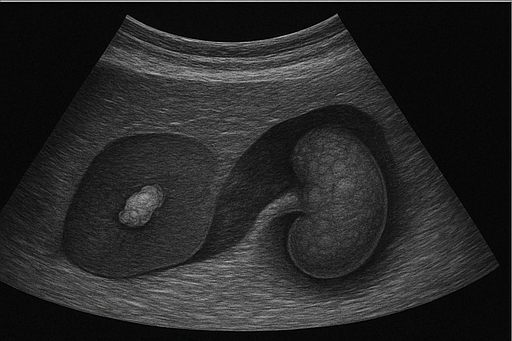

신장 및 비뇨기계

- 신장 결석: 신장에 생긴 돌로, 초음파에서 밝은 음영과 그림자로 나타납니다.

- 신장 종양: 신장에 발생하는 종양으로, 크기와 모양의 변화를 통해 의심할 수 있습니다.

- 방광 질환: 방광 벽의 두꺼움이나 내부의 종괴 등을 초음파로 확인할 수 있습니다.

담낭 및 담관

- 담석: 담낭이나 담관에 생긴 돌로, 초음파에서 밝은 음영과 그림자로 나타납니다.